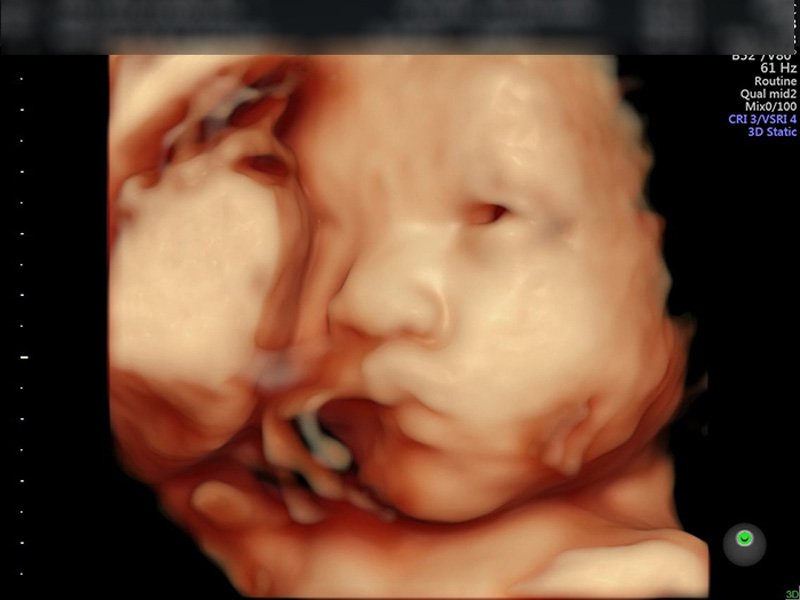

Đây cũng là thời điểm quan trọng để mẹ bầu kiểm tra sức khỏe và theo dõi sự phát triển thai nhi thông qua siêu âm.

Tháng 6: Bé Có Hình Dáng Gần Giống Trẻ Sơ Sinh

Tháng thứ sáu đánh dấu sự phát triển mạnh mẽ:

- Mắt bé mở ra, da bắt đầu dày lên, tóc và lông mày mọc dày hơn.

- Bé bắt đầu có thể nghe thấy âm thanh bên ngoài. Bé có thể phản ứng với ánh sáng và âm thanh.